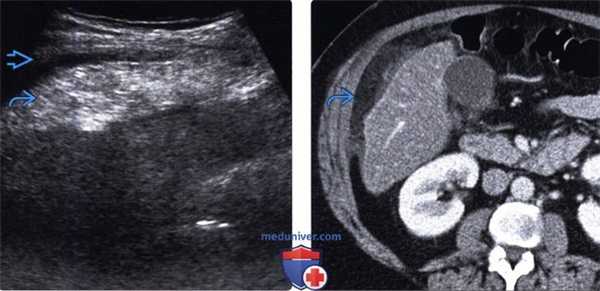

(Левый) Пациент с жалобами на острые боли в правой верхней части живота. При УЗИ брюшной полости в верхнем правом квадранте живота под передней брюшной стенкой определяется эхогенное эллипсоидное образование. Прилегающий желчный пузырь выглядит не измененным (не показан).

(Правый) У этого же пациента при КТ с контрастным усилением на аксиальной томограмме в правом верхнем квадранте живота определяется затенение жировой клетчатки сальника, что соответствует изменениям, выявленным при УЗИ. Обратите внимание на отсутствие видимых изменений прилегающего тонкостенного желчного пузыря.